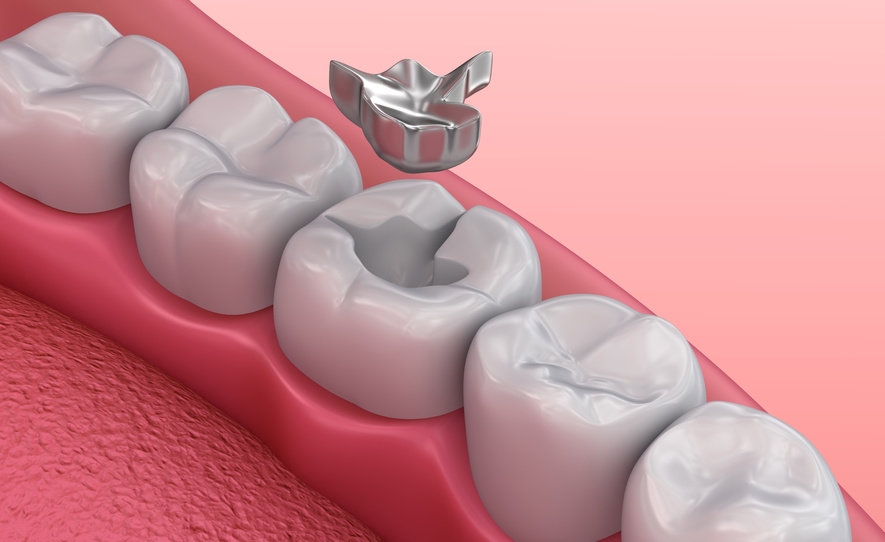

Inlays

Inlays are indirect tooth fillings and are suitable for repairing minor damage caused by caries. Inlays are always placed in the tooth.

Onlays

If much of the chewing surface of a tooth is damaged or destroyed, an onlay is placed on top of the tooth.